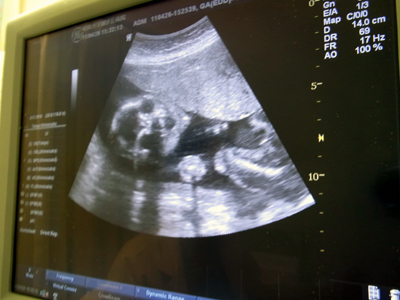

エコーでの検査。

頭囲から脳の大きさ、いろいろと測っていく。

機械自体は通常診療のそれと同じだが、

通常診療より細かく診てゆくのだそう。

もうずいぶんと大きくなっている。

手足の位置はおろか、口の動きまでよくわかる。

あくびしている。

胴回りがちょっと太いかな・・・。

通常胎児には必要な分の栄養しか行かないのであるが、

母胎の栄養状態が良いと、胎児の栄養も過多になってしまうことがあるらしい。

他、心臓も問題がないようだ。

腸は・・・?

腸に何かあるとか、詳しくわかるのは30週を越えてから。

今ここで何か見つかったら、重症だ。

逆に今何もないので、大きな問題はないと考えてもらってよいだろう。

との事であった。

性別は、向きが悪くまた足も組んでいるようで、

何度かトライしたが、はっきりとはわからなかった。

しかし先生の印象としては、

付いているような気がします・・・。

ヨレている臍の尾だって見えるのに、

モノ見えず。

最後に総括を。

胴回り以外は問題はないでしょう。

やはりそこですか